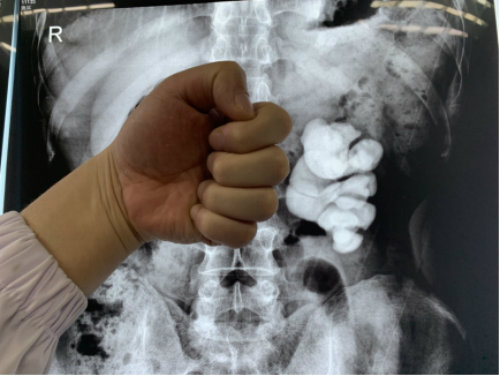

2019年11月26日,湖北蘄春的周先生在武漢京都結(jié)石醫(yī)院成功保腎取出左腎里近十公分的拳頭大結(jié)石,堪稱微創(chuàng)取石領(lǐng)域的典范案例。

近日,周先生慕名趕到專門治結(jié)石的武漢京都結(jié)石醫(yī)院。完善相關(guān)檢查后,醫(yī)生初步判定其左腎還有部分功能,決定為他放手一搏。盡管手術(shù)難度大,術(shù)中出現(xiàn)大出血和腎內(nèi)壓過高導(dǎo)致的穿刺時(shí)腎破裂的概率極高,但在該院多科室專家的全力救治下,周先生最終如愿保住了左腎,拳頭大的結(jié)石也被處理了。